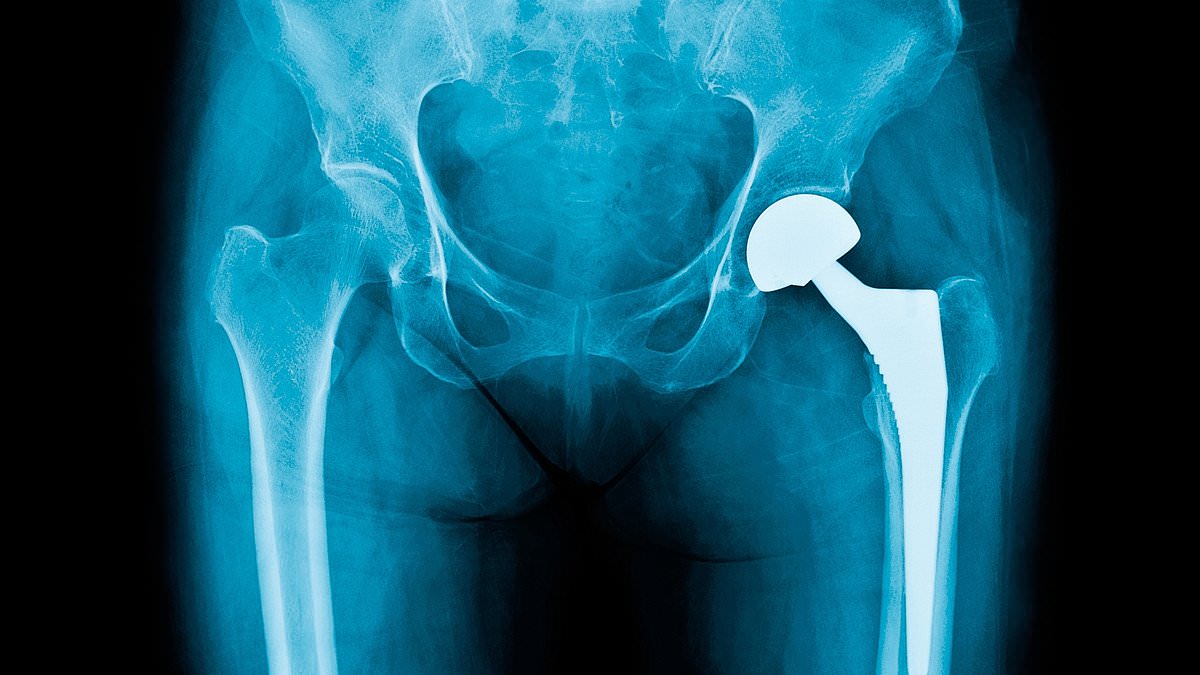

At the heart of the crisis lies a technological bottleneck. Bone cement, used in over 80% of knee replacements and 60% of hip procedures, is essential for securing implants and enabling patients to recover quickly. Heraeus, the NHS's preferred supplier, has warned of a two-month shortage due to its system upgrade. While alternative manufacturers exist, experts like Dr. Alex Dickinson of the University of Southampton emphasize that no substitute can replicate the material's properties without extensive testing. 'Implant engineering is a cautious process,' he explains, 'and new technologies carry risks that require years of follow-up to understand.'

The lack of alternatives has left the NHS in a tight corner. With only 18% of procedures using other types of cement, and alternative suppliers struggling to meet demand, the shortage could persist for far longer than two months. Fergal Monsell, president of the British Orthopaedic Association, admits that the crisis is beyond the control of surgeons and NHS trusts. 'We're working to reduce the impact,' he says, 'but the problem is now.'